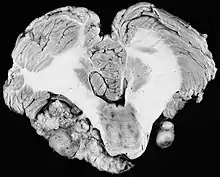

Bilateral schwannomas in a patient with neurofibromatosis 2

For the most part, unilateral sporadic vestibular schwannomas are readily treated successfully by modern medical techniques. Having bilateral VSs is a more troublesome condition. Bilateralism is considered to be the hallmark and main diagnostic criterion of Neurofibromatosis Type II (NF2), a genetic disorder that is heritable, progressive, difficult to manage, and has a 1 in 2 chance of being passed on to each offspring. NF2 patients tend to have a more severe mutation, although there are mild mosaic cases in which only some cells carry the mutation. Genetic testing confirming mutation of the NF2 gene is recommended. About 50% of people with NF2 have a de novo mutation, and about 50% of these new mutations will be mild mosaic cases which are less likely to be passed on. NF2 patients may develop other cranial and spine tumors. NF2 develops during the teens or early adulthood, whereas sporadic VSs are diagnosed mostly in patients between the ages of 40–60 years. Both varieties of VS (sporadic and NF2) are very rare, accounting for only about 8% of all primary brain tumors. The incidence of NF2 is approximately 1 per 60,000 people.[6][7][8]